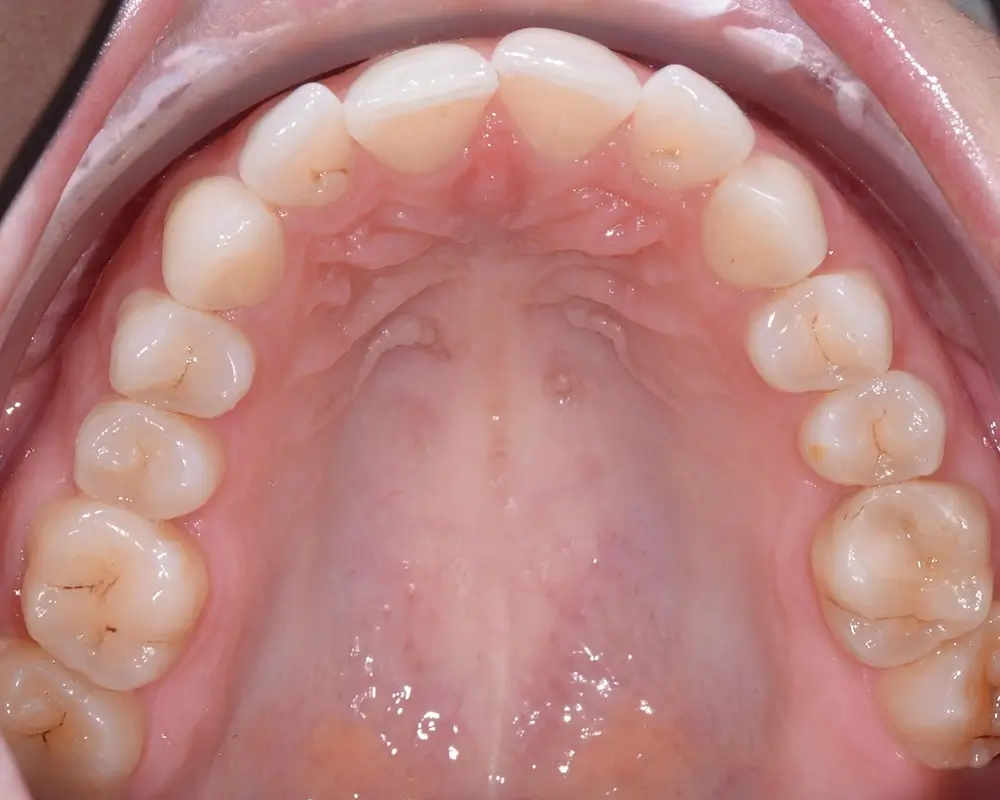

Дистальный прикус - Кейс 4

Эффективность устранения дефекта прикуса посредством элайнеров FlexiLigner.

26

Количество кап НЧ

18

Количество кап ВЧ

Результаты лечения